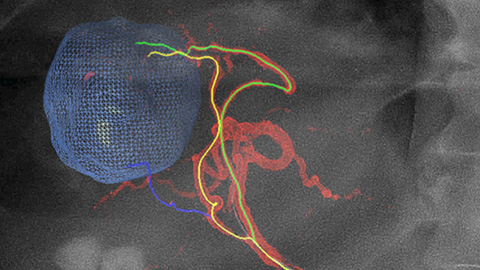

EmboGuide supports you in maximizing the efficacy of your TACE procedures as it potentially enhances your sensitivity, reduces false positives and maximizes inter-reader agreement [4]. It provides efficient, workflow-based live 3D guidance with automatic feeder detection [5].

ClarityIQ produces tuned, high definition low dose images with superb vascular detail to monitor the embolization [6].

A post embolization 3D acquisition allows you to visualize the targeted deposition of embolic material, such as Liopidol or radiopaque beads, in the tumor [7].

Dual View allows simultaneous visualization of pre-embolization arterial phase 3D image and the post embolization image to assess treatment endpoint and predict outcome.